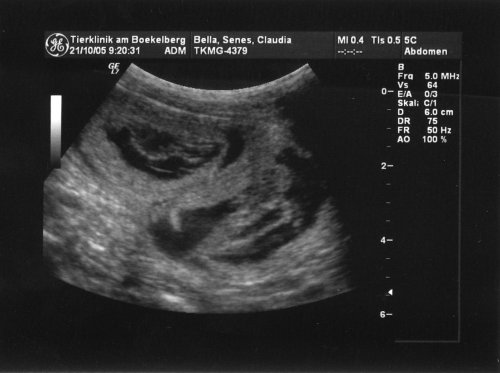

Das Ultraschallbild hat es dann eindeutig gezeigt: Mindestens fünf Föten haben es sich in Bellis Gebärmutter gemütlich gemacht, vermutlich sogar noch einige mehr.